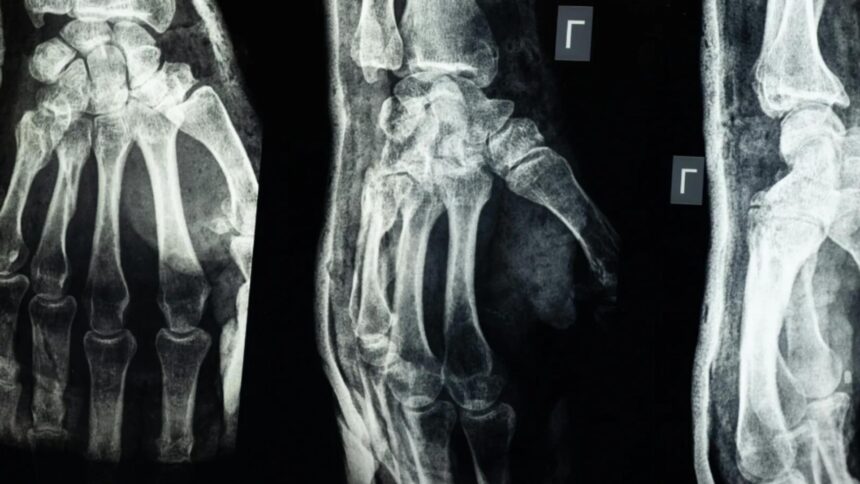

O echipă de cercetători din provincia Zhejiang, China, a dezvoltat un adeziv medical numit „Bone-02”, capabil să repare fracturile osoase în doar 2-3 minute. Acesta are potențialul de a înlocui implanturile metalice utilizate în prezent și de a reduce semnificativ perioada de recuperare a pacienților.

Testele de laborator și studiile clinice efectuate pe peste 150 de pacienți au demonstrat că „Bone-02” oferă o rezistență similară cu cea a implanturilor metalice, cu o forță de lipire care depășește 400 de livre și o rezistență la compresiune de aproximativ 10 MPa.